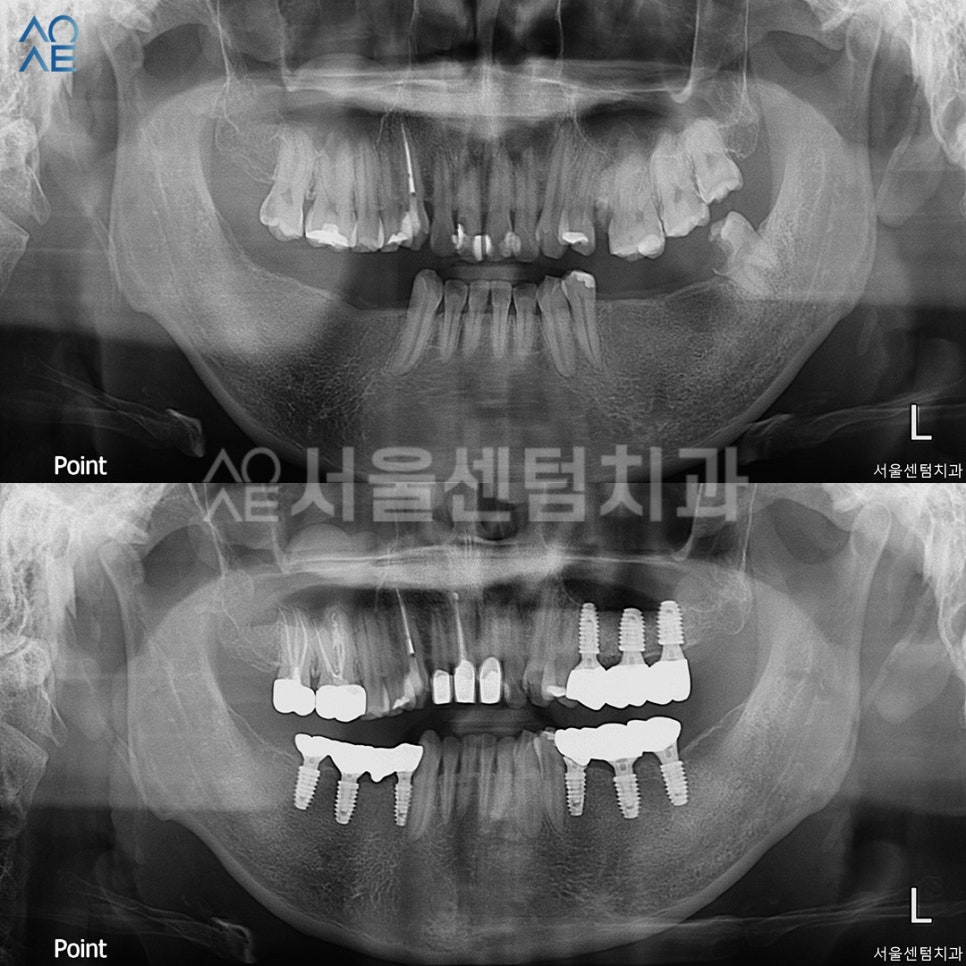

1년 넘게 내원하시면서

임플란트와 신경치료를 마무리했고

이 엑스레이는 정기검진때 촬영했습니다.

성공적인 30대임플란트 결과

이렇게 전/후 사진을

나란히 놓고 보니 차이가 확연하네요.